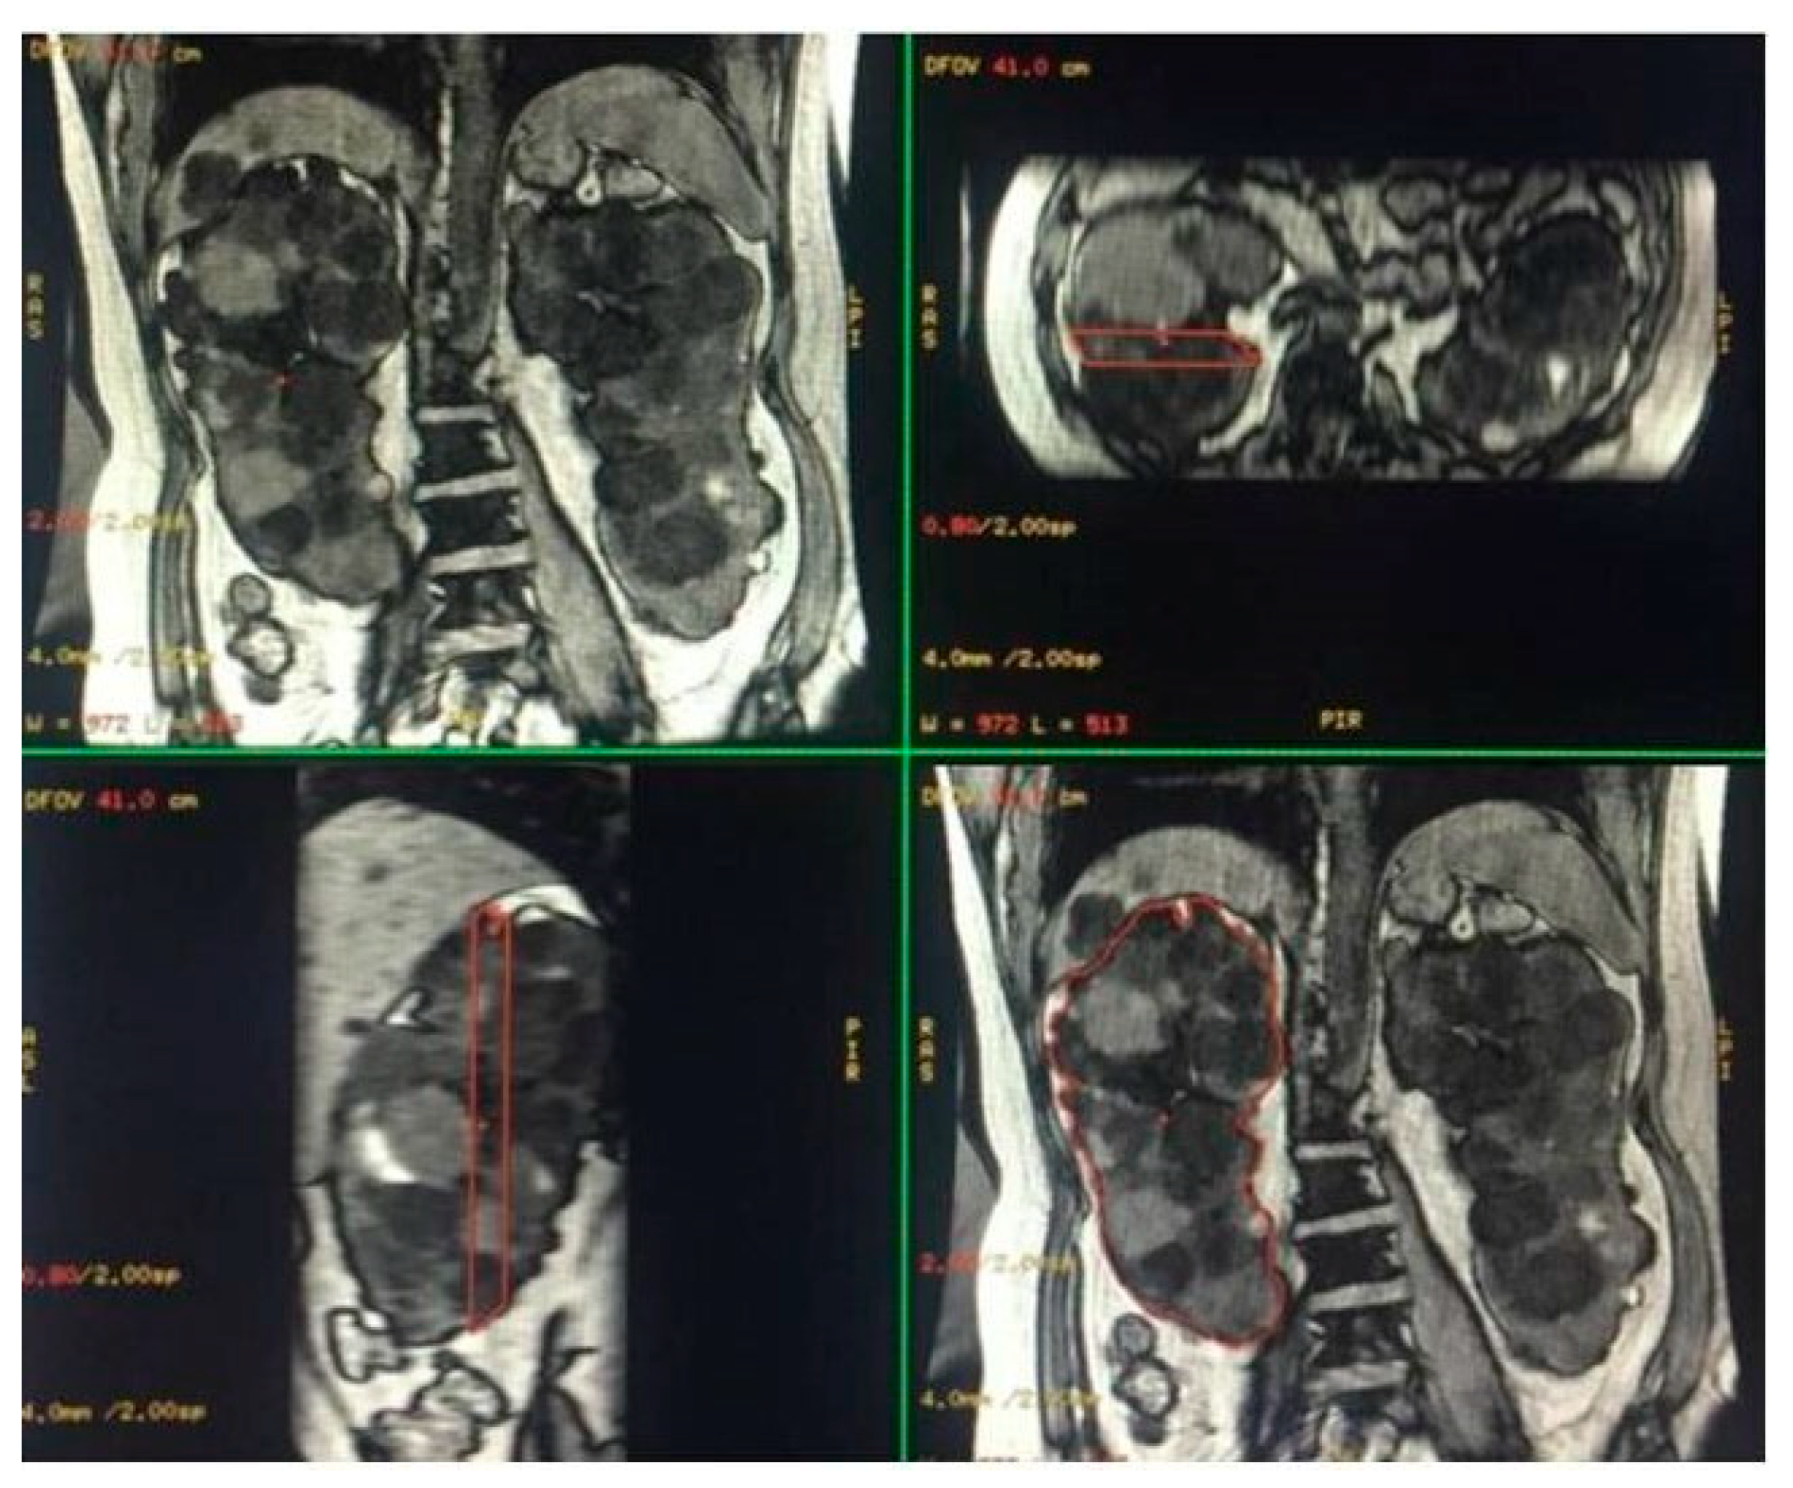

Figure 2.

Semi-automatic volumetric segmentation. View of images in the three planes of space during segmentation.